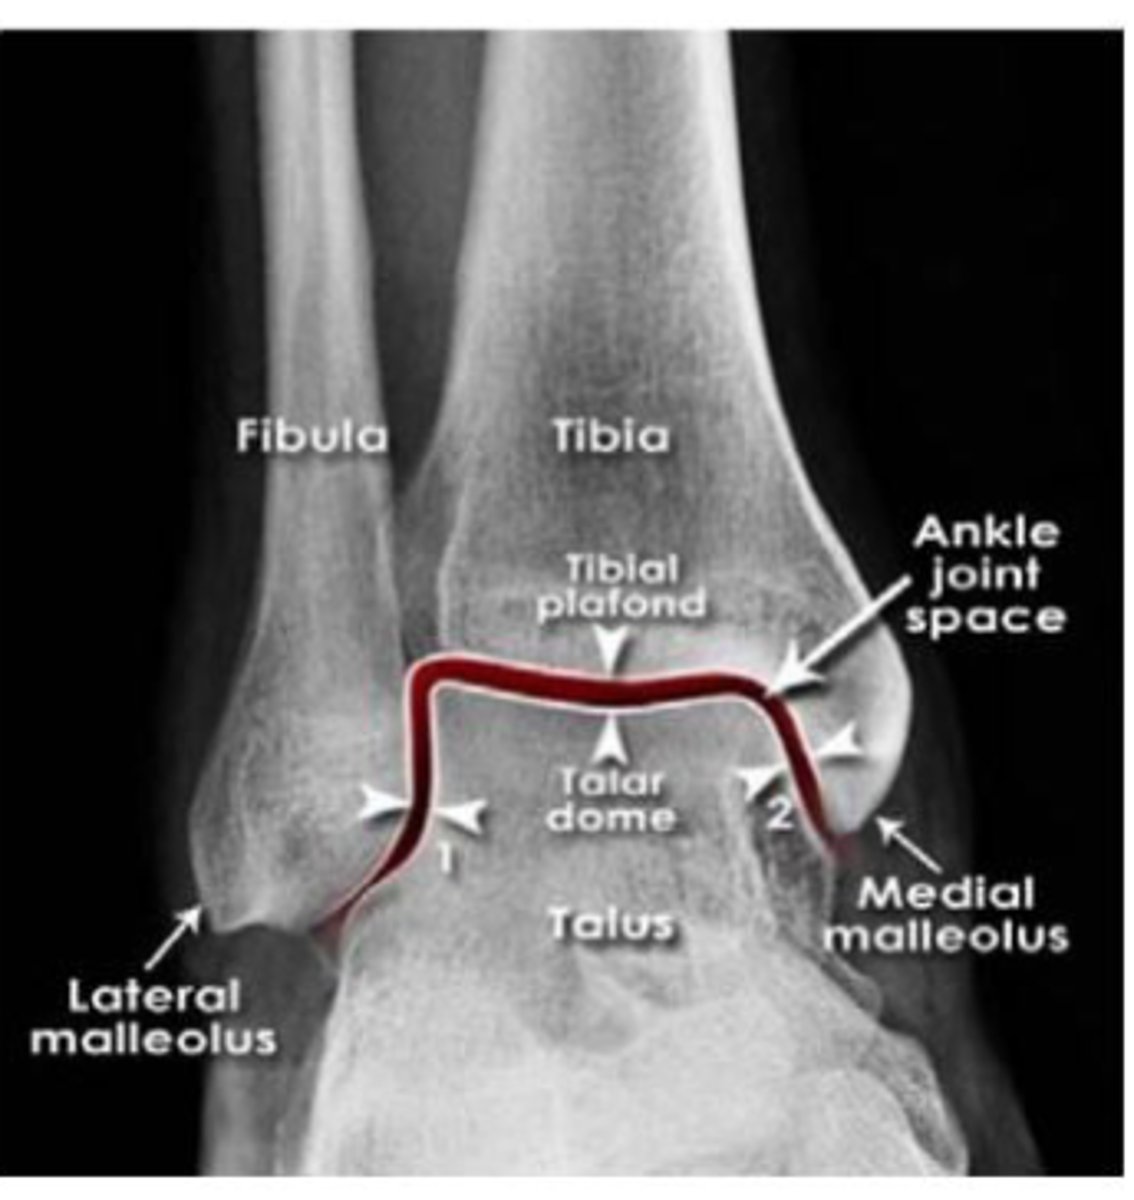

ankle

knowt flashcard image